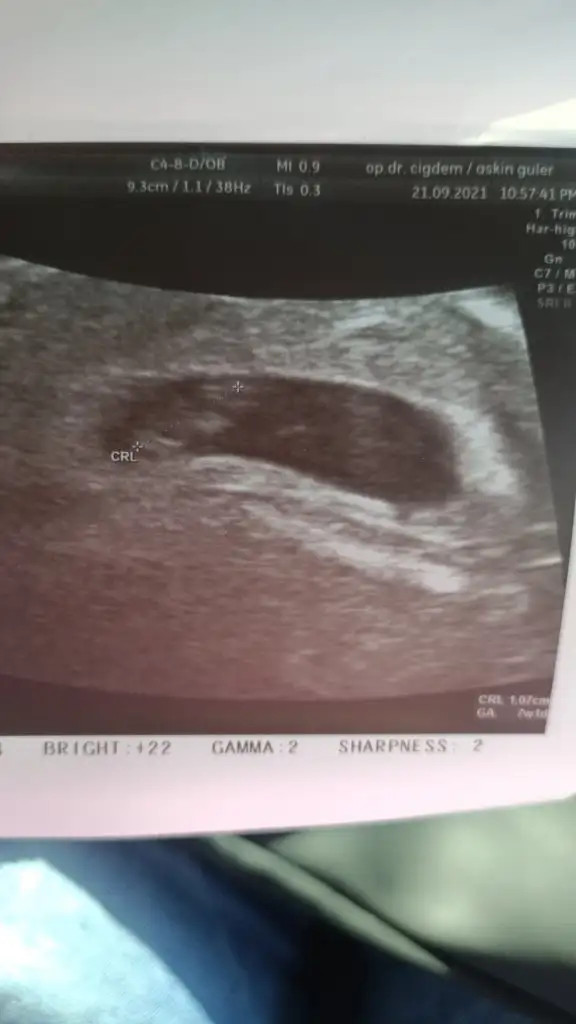

Ben kalp atışını duydum. Daha dogrusu duyamadim, gördüm sadece. Ayrıca biz degil ben

Neyse iste bugun devlet hastanesindeki hanim doktoda gittim, bi de tavsiye etmisti birkac kisi yani. Neyine bakip tavsiye ediyolar anlamiyorum. Esimi almadilar iceri, cok moralim bozuldu. O da duysun istemistim. Neyse zaten ben de duyamadim. Ses yoktu cihazda. Ekranda pıt pıt oynayan bisey gosterdi. Bak bu kalbi atiyor sorun yok dedi, yallah. Hicbisey soramadim bile. Hic memnun kalmadim. Ilcede oturmak ne kotuymus ya Cok canımı sıktı doktor bulamama olayi